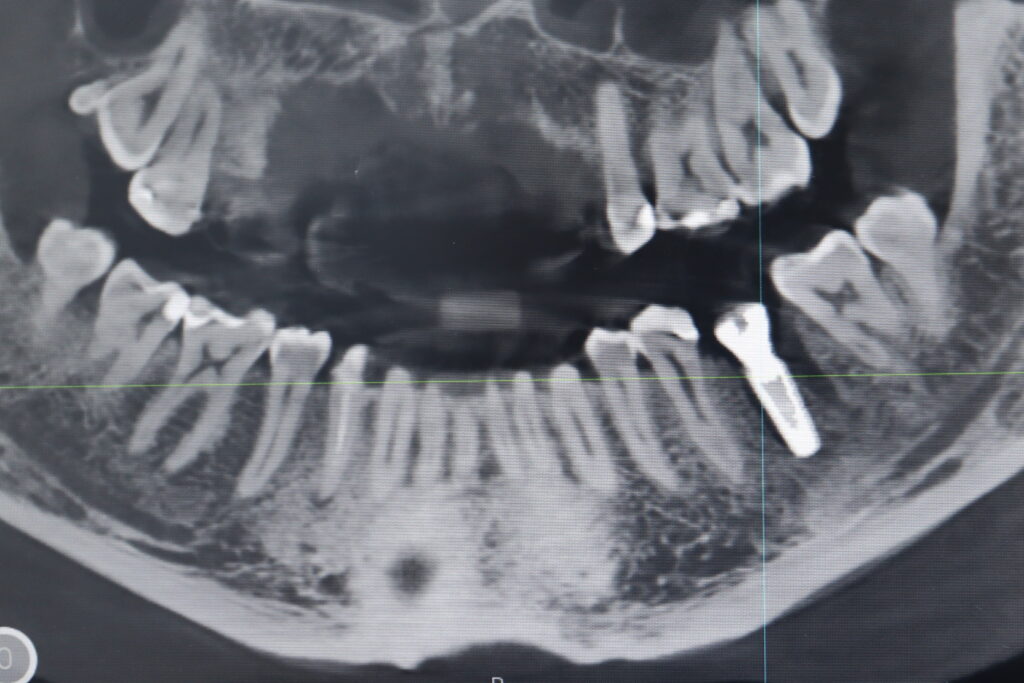

Ситуация до лечения

Жалобы: Пациент обратился с жалобами на воспаление в области зуба 3.6. После обсуждения плана лечения, пациентом было принято решение об имплантации.

Диагноз: Хроничекий апикальный периодонтит.

пациент до имплантации